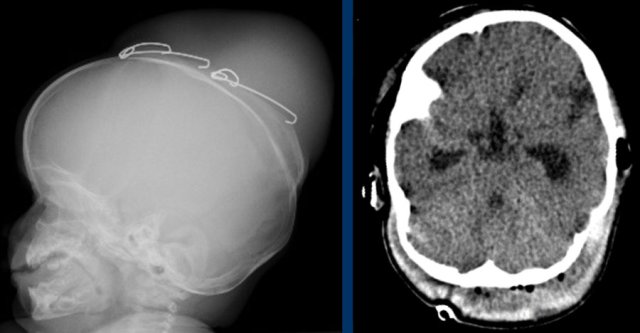

Images

Raised intracranial pressure.

LEFT: Impressions on a skull radiograph have a low sensitivity, especially in young children, but when seen, are highly suspicious for raised intracranial pressure.

RIGHT: Hydrocephalus with inverted diastolic flow indicating high intracranial pressure.

The images are of a patient with increased intracranial pressure.

There is tonsillar herniation with severe crowding at the craniocervical junction.

This has resulted in a syrinx over the entire length of the spinal cord.